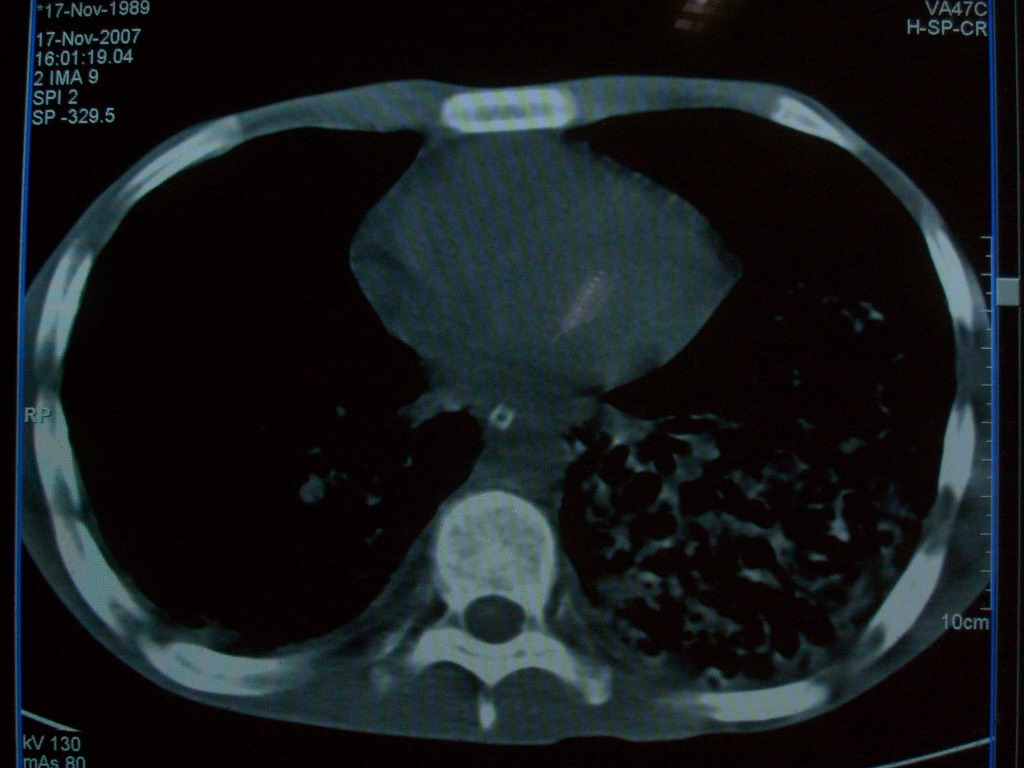

标题: CT10510:男.18岁,咳嗽咳痰两月.(有病理) [打印本页]

标题: CT10510:男.18岁,咳嗽咳痰两月.(有病理)

双肺布满大片状实变及网格状结节影,内参杂大小不等的气囊及空气支气管征,心脏增大。考虑:1 全身结缔组织疾病—系统性红斑狼仓?2 肺泡蛋白沉积症合并感染!

双肺布满大片状实变及网格状结节影,内参杂大小不等的气囊及空气支气管征,双侧胸膜腔少量积液,双下肺近膈面透亮度尚可,病人较年轻,病变较重(不知为什么上胃管?)考虑:1.胶原病肺部改变,2.组织细胞病x。结合实验室检查。

首先考虑组织细胞x病。两肺中上肺野多发囊腔,中下肺野内见多发小结节,并可见肺间质增厚。患者是男性,年龄较小。胶原性病变比较多见的类风湿、系统性红斑狼疮和硬皮病临床和影像均不是很支持,类风湿和系统性红斑狼疮的肺部表现最常见的是胸腔积液,硬皮病可见食管的扩张。

肺内多发斑片状、结节状、融合大片状及网格状影,多发薄壁空腔影,胸膜肥厚,纵隔、气管右移,考虑ⅲ型肺结核,多发空洞,继发肺间质纤维化。

双肺结核并播散.患者以肠梗阻入院,手术为肠结核.术后咳嗽做ct检查.